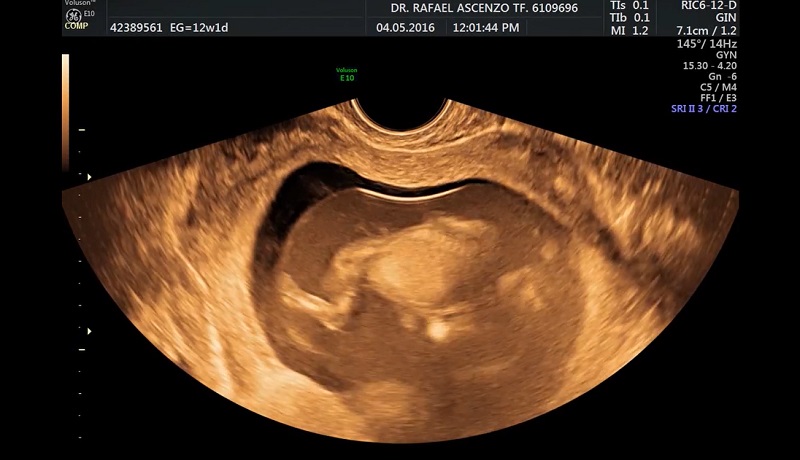

Desde hace unos cuantos años, la Medicina está realizando enormes progresos en el conocimiento de lo que sucede antes del nacimiento. Los avances científicos, como las ecografías, confirman cada vez más que el aborto es un crimen. Algunos de estos avances son claros hasta para un profano en la materia:

Muchos padres y abuelos llevan en sus automóviles la foto de la ecografía de sus hijos y nietos a los que les falta todavía bastante para nacer. Pero no es sólo por las ecografías. Los avances científicos médicos van todos en la misma dirección. En el Manifiesto de Madrid del 2009, encabezado por científicos de la talla de Nicolás Jouve y César Nombela, varios miles de intelectuales españoles se pronunciaron sobre el aborto. Los párrafos más interesantes son :

Hoy existe tecnología avanza y con ello se puede lograr muchas cosas en favor de la salud. La imagen muestra una ecografía 6D ha captado la sonrisa de un bebé dentro del vientre materno